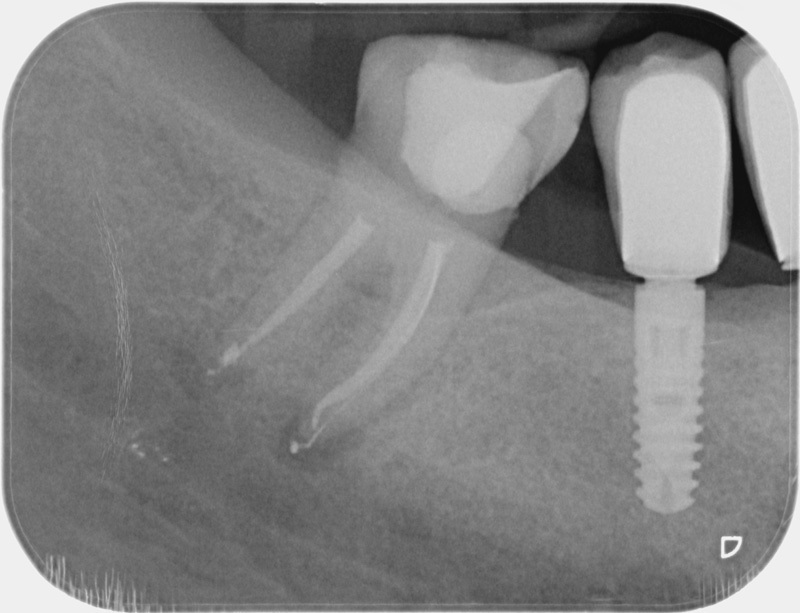

• Reprise de traitement endodontique : La manœuvre consiste à retourner à l’intérieur des racines d’une dent déjà traitée. Il arrive occasionnellement qu’une nouvelle inflammation se déclare suite à une reprise de carie ou une fracture de la dent, ou si le premier traitement endodontique est incomplet. Après s’être assuré que la dent lésée était conservable, il convient de désinfecter de nouveau le réseau canalaire parfois très complexe. La nouvelle obturation des canaux devra être protégée aussi rapidement que possible pour éviter une éventuelle contamination bactérienne.

Avant